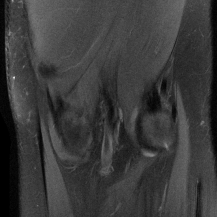

| Ground Truth | Global | LONDN-MRI | LONDN-MRI | Oracle |

| (1 iteration) | (2 iterations) | |||

![]() |

| PSNR = dB | PSNR = 29.26 dB | (d) PSNR = 29.50 dB | PSNR = 29.68 dB | (f) PSNR = 29.72 dB |

| Initial | DIP | SOUP-DIL | RAKI | LORAKI |

| PSNR = 16.43 dB | PSNR = 27.50 dB | (d) PSNR = 28.16 dB | PSNR = 28.32 dB | (f) PSNR = 28.72 dB |